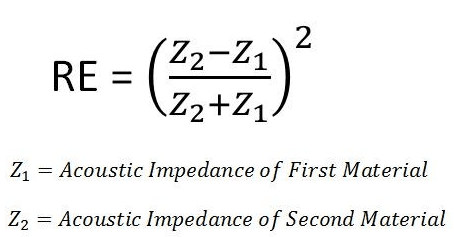

It is often said that “air is the enemy of ultrasound.” This is due to the principle of acoustic impedance (Z), which mathematically demonstrates that the greater the impedance between two media, the greater the reflected energy (RE) of the sound wave, ultimately making ultrasonography a ‘sticky’ business.

Ultrasound gel allows us to see into the body by bridging the impedance gap between the skin and air. The body also contains air filled structures that can be difficult to see. Last month, we explored lung ultrasonography, but a new year brings new frontiers and we are excited to bring to you gastric ultrasonography.